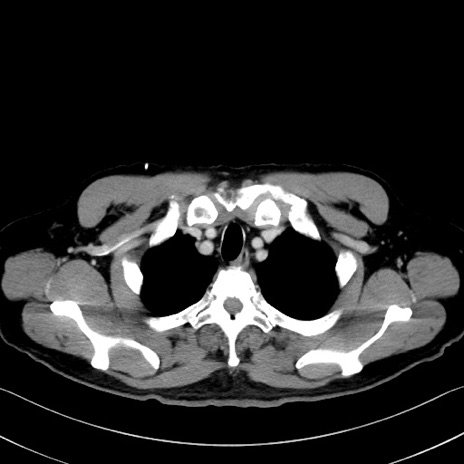

症例35(横断像)

【症例】70歳代 男性

【主訴】腹部膨満、嘔吐

【現病歴】昨日より腹部膨満感出現。本日増悪し、仙痛出現。嘔吐あり、受診。

【既往歴】糖尿病、胆摘後

【身体所見】BP 149/80mmHg、HR 74/min、BT 35.9℃、腹部:膨満、軟、圧痛なし。腸雑音減弱あり。上腹部正中切開瘢痕あり。

【データ】WBC 13500、CRP 1.72